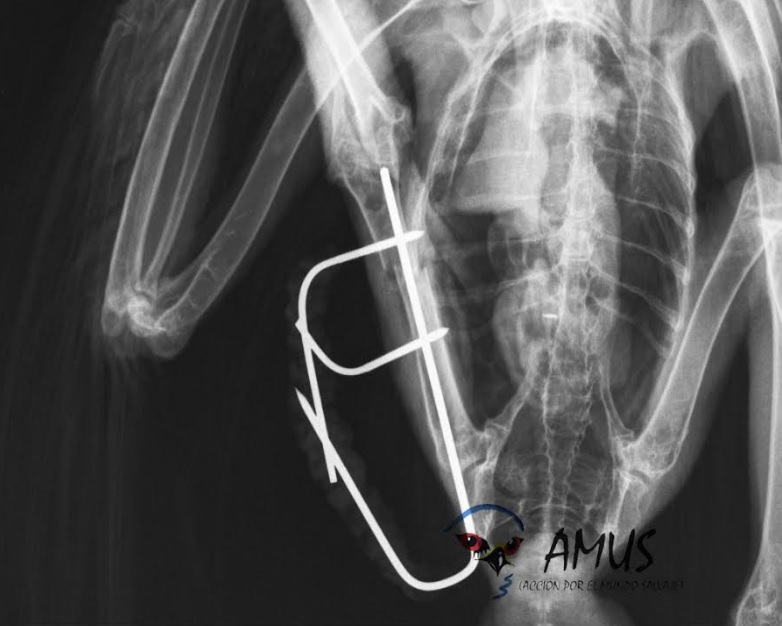

El sábado 23 de septiembre a las 19 h te esperamos en la ermita de San Isidro, en Hornachos (Badajoz) donde liberaremos varios animales ingresados y recuperados en nuestro hospital. Entre ellos está un águila culebrera que ingresó tras ser disparada y va provista de un emisor satélite que nos permitirá conocer su vida, sus desplazamientos, su adaptación y de cómo puede también afectarle los desordenes climáticos en la elección de sus territorios.